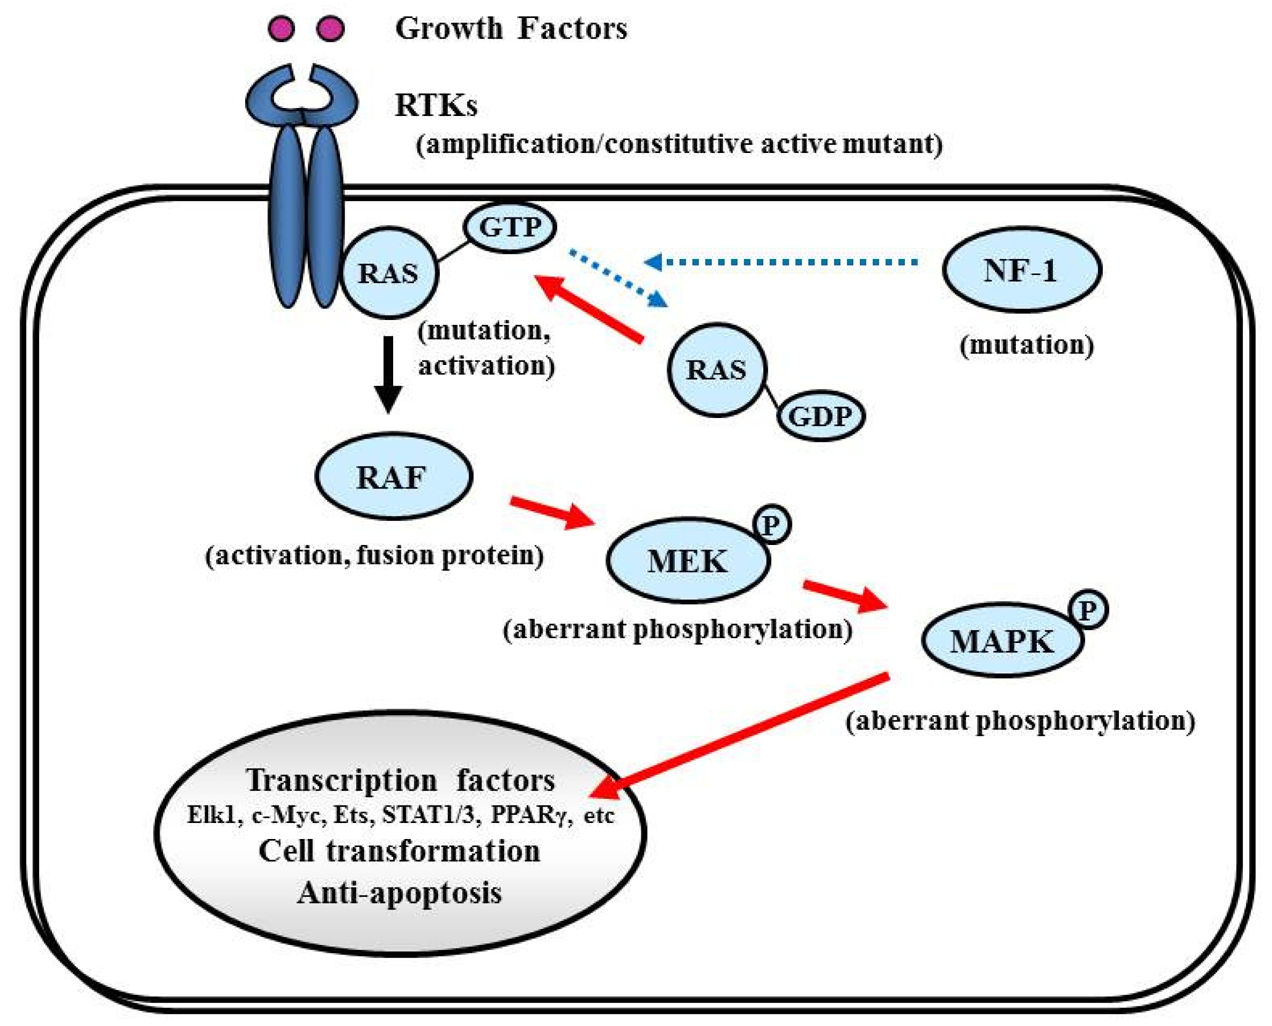

Proliferative activity with histopathologically detectable mitoses is prominent in almost all GBM cases. It is essential to define the contribution of proliferation signaling (or growth factor-mediated signaling) to the GBM cellular phenotype in order to understand the biology of transformation in the CNS. Two of the most important signaling cascades frequently deregulated in glioma are the PI3K/Akt/mTOR and Ras/MEK/MAPK pathways (Figure 3).

7.4. Ras/MAPK Pathway

The NF-1 tumor suppressor gene encodes neurofibromin, which functions primarily as a RAS negative regulator and plays a role in adenylate cyclase- and Akt-mTOR-mediated pathways [147,148] (Figure 8). There is increasing evidence that the NF-1 gene is involved in the tumorigenesis of not only NF-1-related but also sporadically occurring gliomas. In the TCGA pilot study, NF-1 mutation/homozygous deletions were identified in 18% of GBM [1]. Mesenchymal GBMs, having frequent inactivation of the NF-1 (37%), p53 (32%), and PTEN genes, respond to aggressive chemo-radiation adjuvant therapies [90].

7.4.2. RAS

RAS activates the STKs Raf, MAPK (ERK1 and ERK2), PI3K, and a number of proteins that translocate to the nucleus to promote cell proliferation, differentiation, and survival (Figure 8). The RAS gene family comprises four different genes that encode HRAS, NRAS, KRAS4A, and KRAS4B [149,150]. Combined activation of RAS and Akt in neural progenitors induces GBM formation in a mouse model [46]. Although activating RAS mutations are observed in approximately 30% of human cancers [149], the RAS mutations are rare in human GBM (2%, according to the TCGA study [1]). Therefore, the observed deregulation of the Ras/RAF/MAPK signaling pathway in GBM is attributed to its upstream positive regulators, including EGFR and PDGFR, which are highly active in the majority of malignant gliomas [87,151].

7.4.3. RAF

Activated RAS recruits RAF kinase to the membrane, where it is activated by multiple phosphorylation events (Figure 8). The RAF family of STKs, which consist of ARAF, BRAF, and CRAF1, play an important role in proliferative signaling. In pediatric low-grade glioma, consisting of pilocytic astrocytoma and fibrillary astrocytoma, chromosome 7q34 rearrangements result in an in-frame KIAA1549:BRAF fusion gene that possesses constitutive BRAF kinase activity resembling oncogenic BRAF (V600E) [152]. In contrast, RAF mutations or rearrangements are rare in malignant gliomas in adults. A phase I/II clinical trial is currently underway for recurrent GBM with combined Raf and mTOR inhibiters, Sorafenib (NexavarR, Bayer, and Onyx, Emeryville, CA, USA) and temsirolimus (CCI-779) (NCT00335764).

7.4.4. MEK/MAPK

Activated RAF phosphorylates and activates MAPK kinase (MAPKK), also called MEK, which in turn phosphorylates and activates MAPK [153]. Activated MAPK translocates into the nucleus to activate several transcription factors such as Elk1, c-myc, Ets, STAT (signal transducers and activators of transcription) 1/3, and PPARγ (peroxisome proliferator-activated receptor γ), which induce cell cycle progression and anti-apoptosis genes [154,155] (Figure 8). Aberrant signaling through this pathway leads to cell transformation and resistance to apoptosis; thus, this pathway is an attractive target for malignant glioma therapy [156].